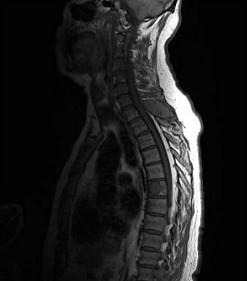

常见的椎管内肿瘤(如图所示)有()A.脊膜瘤B.胶质瘤C.血管瘤D.上皮样囊肿E.神经鞘瘤

问题 常见的椎管内肿瘤(如图所示)有()

选项 A.脊膜瘤 B.胶质瘤 C.血管瘤 D.上皮样囊肿 E.神经鞘瘤

答案 ABCDE